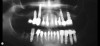

Fig 10. Radiographic view of a heavily restored 37-year-old patient revealing numerous problems associated with the teeth and implant-supported restorations.

Figure 10

Fig 11. Clinical retracted view of the reconstruction. Notice the uneven gingival margins and the ill-fitting restorations.

Figure 11